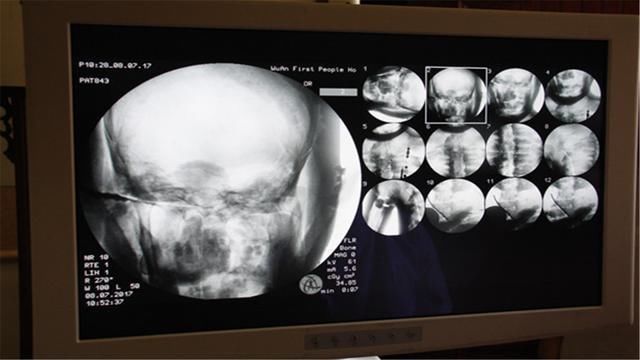

【 至今|千年前河北一高僧坐化,遗体至今不腐,专家用X光扫描后得出结论】2017年,河北省武安市定慧寺主持佛光法师,郑重地将辽代高僧慈贤法师的全身舍利捐献给国家。为了了解文物的状况,武安市第一人民医院骨科副主任,武永庆亲自操作x光机,对文物进行了扫描。通过现代化科学仪器,医生透过慈贤法师身上厚厚的香灰泥和金箔,看到了骨骼、牙齿等。

文章插图

武永庆副主任表示:“里面是一具遗体,骨骼完整,呈自然老化现象。与一位70岁左右的老人骨骼,完全一样。”而慈贤法师的头骨,历经千年,依旧坚硬如初。检测结果公布后,引起了社会各大媒体的关注,慈贤法师千年后的体检,再次轰动了全世界。